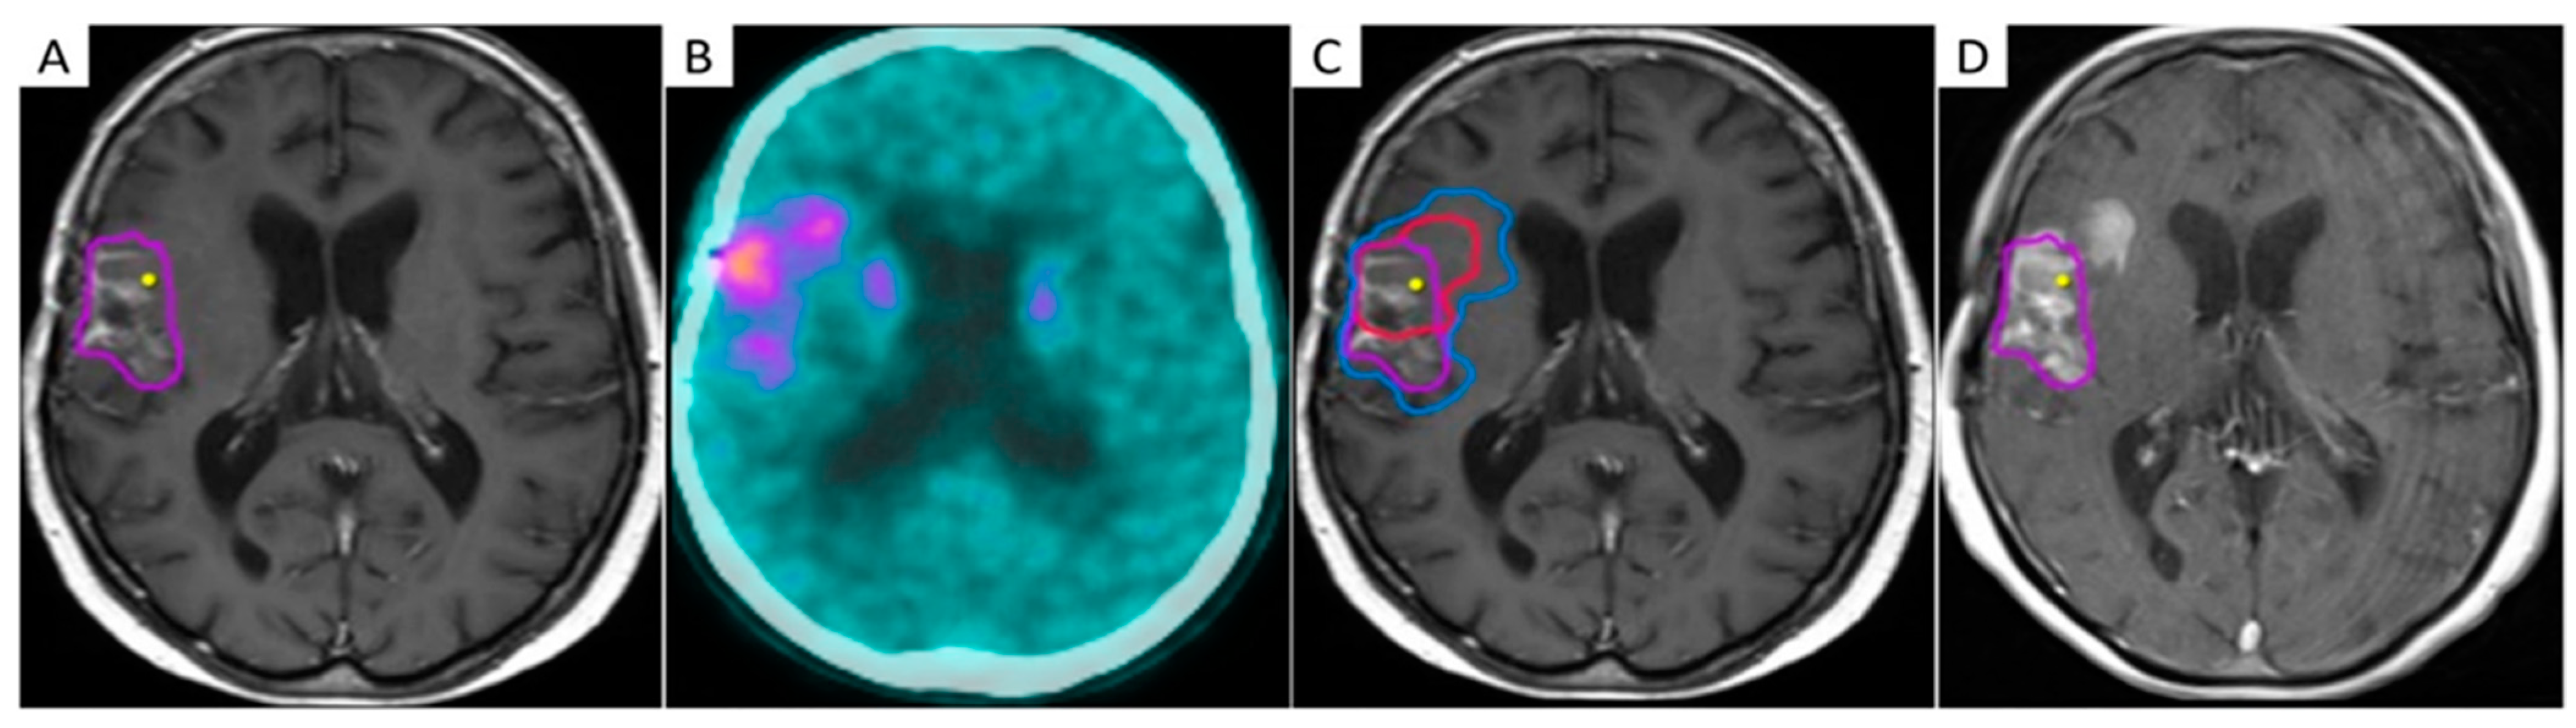

The combination of multiple advanced MRI techniques may enhance their implementation in the RT planning setting (Figure 2). Their integration with dosimetry may help identify voxels at risk for progression and allow voxel-level risk-adapted dose escalation to subclinical disease while sparing normal tissue [101].

Figure 2.

Integration of advanced MRI sequences in a Gamma Knife radiosurgical planning of a 44-year-old male patient with recurrent WHO grade III astrocytoma after multimodal first-line therapy and recent redo surgery with maximum safe resection. Axial (upper row) and coronal (bottom row) views of contrast-enhanced T1-weighted (A) and fluid-attenuated inversion recovery (FLAIR) (B) MRI images, co-registered with relative cerebral blood volume (rCBV) map (C) and apparent diffusion coefficient (ADC) map (D), demonstrating how different sequences identify different volumes of disease. The final target was determined as the nodule showing hyper-intensity in post-contrast T1-weighted sequences, hypo-intensity in ADC maps, and elevated perfusion values on the rCBV map.